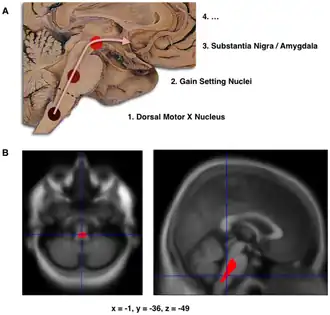

B. Localization of the area of significant brain volume reduction in initial PD compared with a group of participants without the disease in a neuroimaging study which concluded that brain stem damage may be the first identifiable stage of PD neuropathology.[1]

The staging in Parkinson's disease was described by Heiko Braak in 2003.[4] Braak and colleagues state that Parkinson's disease begins when a foreign agent enters the body via the nose or gastrointestinal system and travels into the central nervous system (CNS). The presence of Lewy bodies in the enteric and peripheral nervous systems supports their claim. This Lewy body pathology selectively travels through the CNS, targeting thin and largely unmyelinated neurons. Braak et al., therefore, developed a staging system that characterizes disease progression. This system is divided into six different stages, with each stage being attributed to abnormal pathology in particular neurological structures. In terms of symptomatology, the type and severity of symptoms is correlated to progression through the Braak stages.[5] Early stages are characterized by non-motor symptoms, such as a lessened sense of smell or constipation. Motor symptoms are often displayed around the mid-stage state, and cognitive symptoms arise as later Braak stages are reached.[6] Braak and colleagues further state that the disease begins in the enteric nervous system and gains entry to the CNS through the vagus nerve.[7]

Stage 1

The disease begins in structures of the lower brainstem and the olfactory system. In particular, the dorsal motor nucleus of the vagus nerve in the medulla oblongata and anterior olfactory nucleus are affected.[6] Lewy neurites, thread-like alpha-synuclein aggregates, are more prevalent than globular Lewy bodies in this stage.[4]

Stage 2

In addition to the pathology observed in Stage 1, Stage 2 is characterized by additional lesions in the raphe nuclei and gigantocellular reticular nucleus of the medulla oblongata.[4][6] The disease then moves up the brainstem, traveling from the medullary structures to the locus ceruleus in the pontine tegmentum. Similar to Stage 1, Lewy neurites outnumber Lewy bodies.[4]

Stage 3

At the beginning of Stage 3, the disease has entered the substantia nigra and Lewy body lesions begin to form in the pars compacta.[4][6] The latter half of this stage involves disease progression into the basal nucleus of Meynert, a cluster of acetylcholine-rich neurons in the basal forebrain.[6] Further, structures affected in Stages 1 and 2 begin to develop more Lewy bodies.[4]

Stage 4

Stage 4 is characterized by severe dopaminergic cell destruction in the pars compacta. There is also mesocortex and allocortex involvement; the neocortex remains unaffected. In particular, pathology can be observed in the amygdala and in the subnuclei of the thalamus. There is significant damage done to the anterior olfactory nucleus.[4][6]

Stage 5

The disease has started to invade the neocortex and spreads into the structures of the temporal, parietal, and frontal lobes.[6] Cell death can be observed in the substantia nigra, the dorsal motor nucleus of the vagus nerve, the gigantocellular reticular nucleus, and the locus ceruleus.[4]

Stage 6

The disease has fully invaded the neocortex, affecting the motor and sensory areas in the brain. The disease is at its most severe.[4][6]